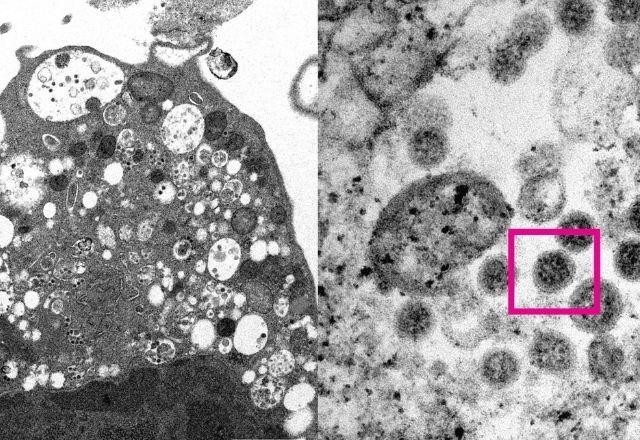

A Universidade de Hong Kong divulgou um comunicado na 4ªfeira (08.dez) informando que sua equipe de cientistas conseguiram registrar uma imagem da variante ômicron do coronavirus por meio de um microscópio. Este é o primeiro registro feito da nova variante que tem capacidade de contágio muito maior que a delta.

O trabalho foi realizado pelos pesquisadores John Nicholls, Malik Peiris e Tam Wah-Ching, que são da Faculdade de Medicina, e eles divulgaram duas imagens dos microscópios, de uma cultura do vírus em laboratório.

A imagem à esquerda está um registro 'de baixa ampliação' de uma célula de rim de macaco, que foi infectada de proposto com a variante ômicron da covid-19.

Além disso, a imagem mostra que a nova variante provoca danos nas células em vesículas, que são as pequenas bolhas, e nelas há muitas partículas virais, que são identificadas pela cor preta.

Do lado direito é possível ver uma imagem ampliada da mesma célula, com as partículas virais mais de perto, registrado pelo quadrado de cor rosa na foto. Neste ponto pode perceber a coroa do coronavírus, que é formada pela proteína S, no entorno da partícula viral.